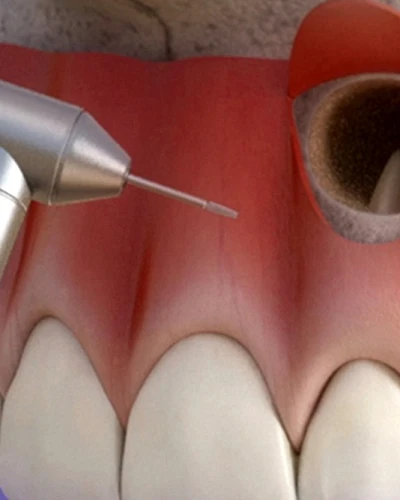

Reendodoncias

Dé una segunda oportunidad a su diente natural con nuestras reendodoncias expertas. Cuando una endodoncia previa no cicatriza o se desarrolla una nueva infección, retiramos meticulosamente el material de obturación anterior, desinfectamos el sistema de conductos con tecnología microscópica avanzada y volvemos a sellar la zona. Nuestro objetivo es eliminar bacterias persistentes y favorecer la curación, evitando la extracción del diente.